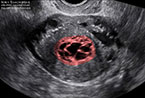

Corps jaune gravidique à 5,5 SA Corps jaune gravide à 5,5 SA Corps jaune gravide à 5,5 SA

Corps jaune gravide à 5 SA Corps jaune gravide à 5 SA Corps jaune gravide à 5 SA